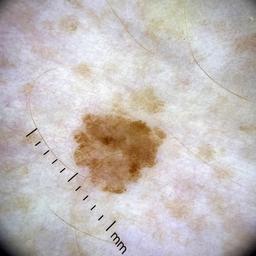

ISIC_5809562

867 x 867

Field Value

acquisition_day 361

age_approx 60

anatom_site_1 Lower extremity

anatom_site_general lower extremity

diagnosis_1 Benign

diagnosis_confirm_type single image expert consensus

image_type dermoscopic